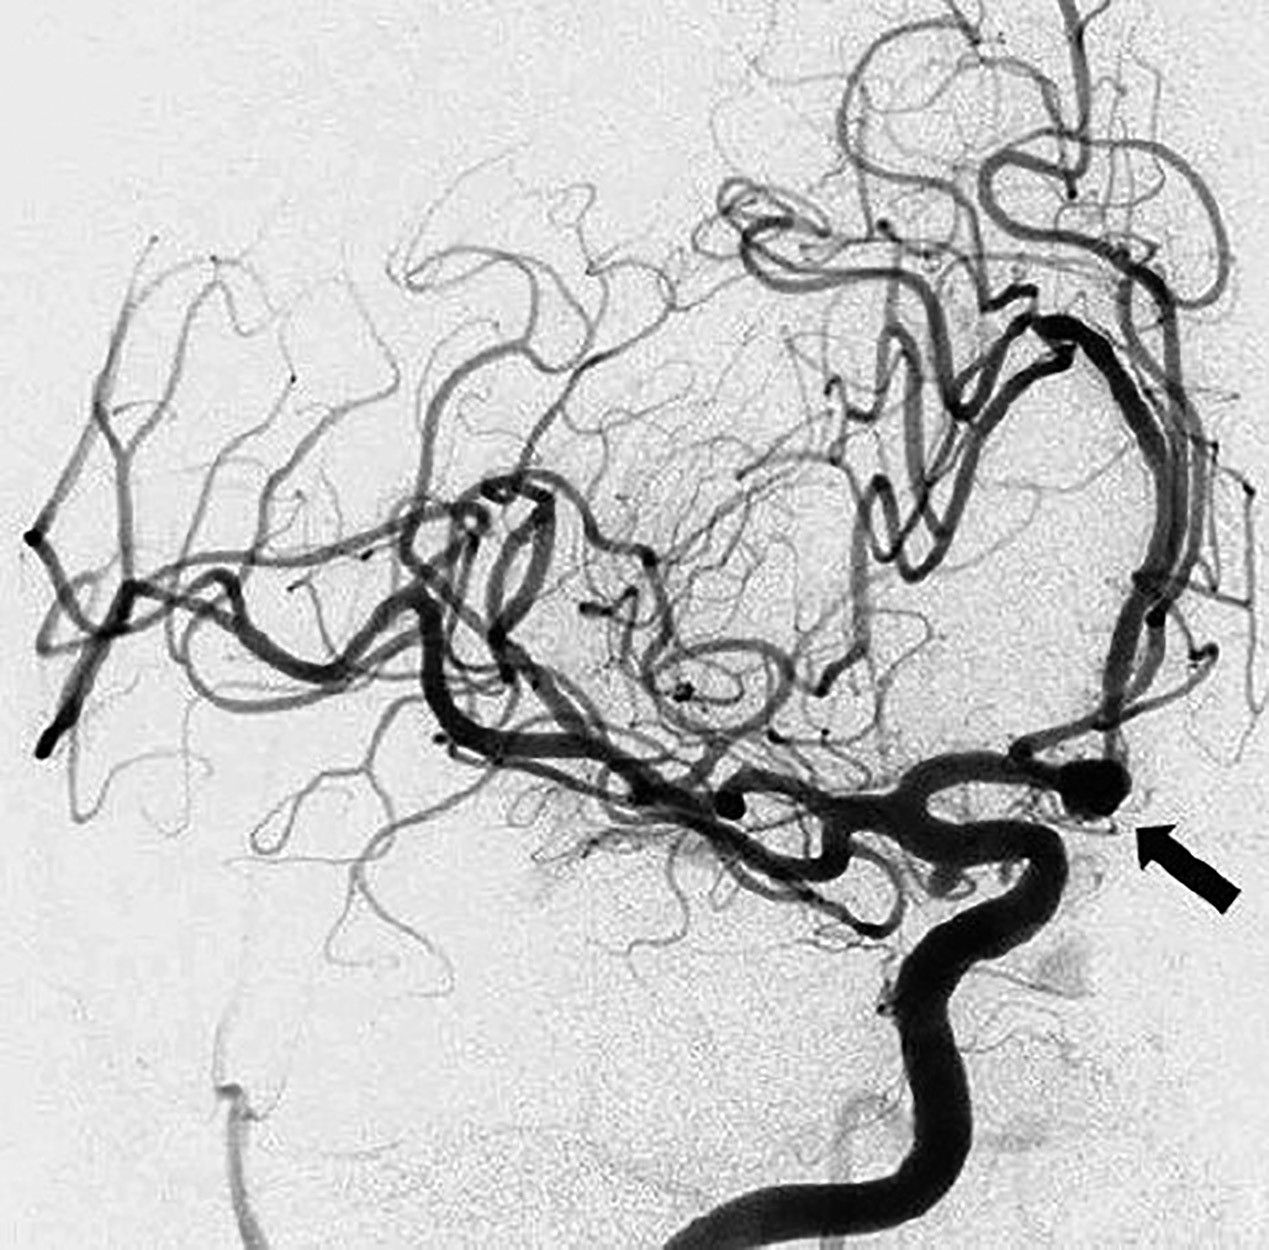

Angiografia cu substracţie digitală (DSA), devenită în momentul de faţă un instrument de importanţă capitală în managementul HSA, presupune injectarea selectivă de material radioopac (substanţă de contrast pe bază de iod), folosind un cateter introdus într-o arteră de calibru mare și studiu radiologic.

Sursa: OpenSource

Reprezintă o investigaţie deosebită în evaluarea anevrismelor cerebrale și se pretează atât ca instrument diagnostic, cât și terapeutic, prin posibilitatea embolizării concomitente a anevrismului sau a malformaţiei arterio-venoase incriminate. Astfel, anevrismele <5 mm sunt ideale pentru coiling (embolizare endovasculară), în timp ce se consideră că pentru restul există un risc mare de recanalizare sau de ocluzie incompletă, astfel că se poate recurge la coiling asistat de stent sau balon.